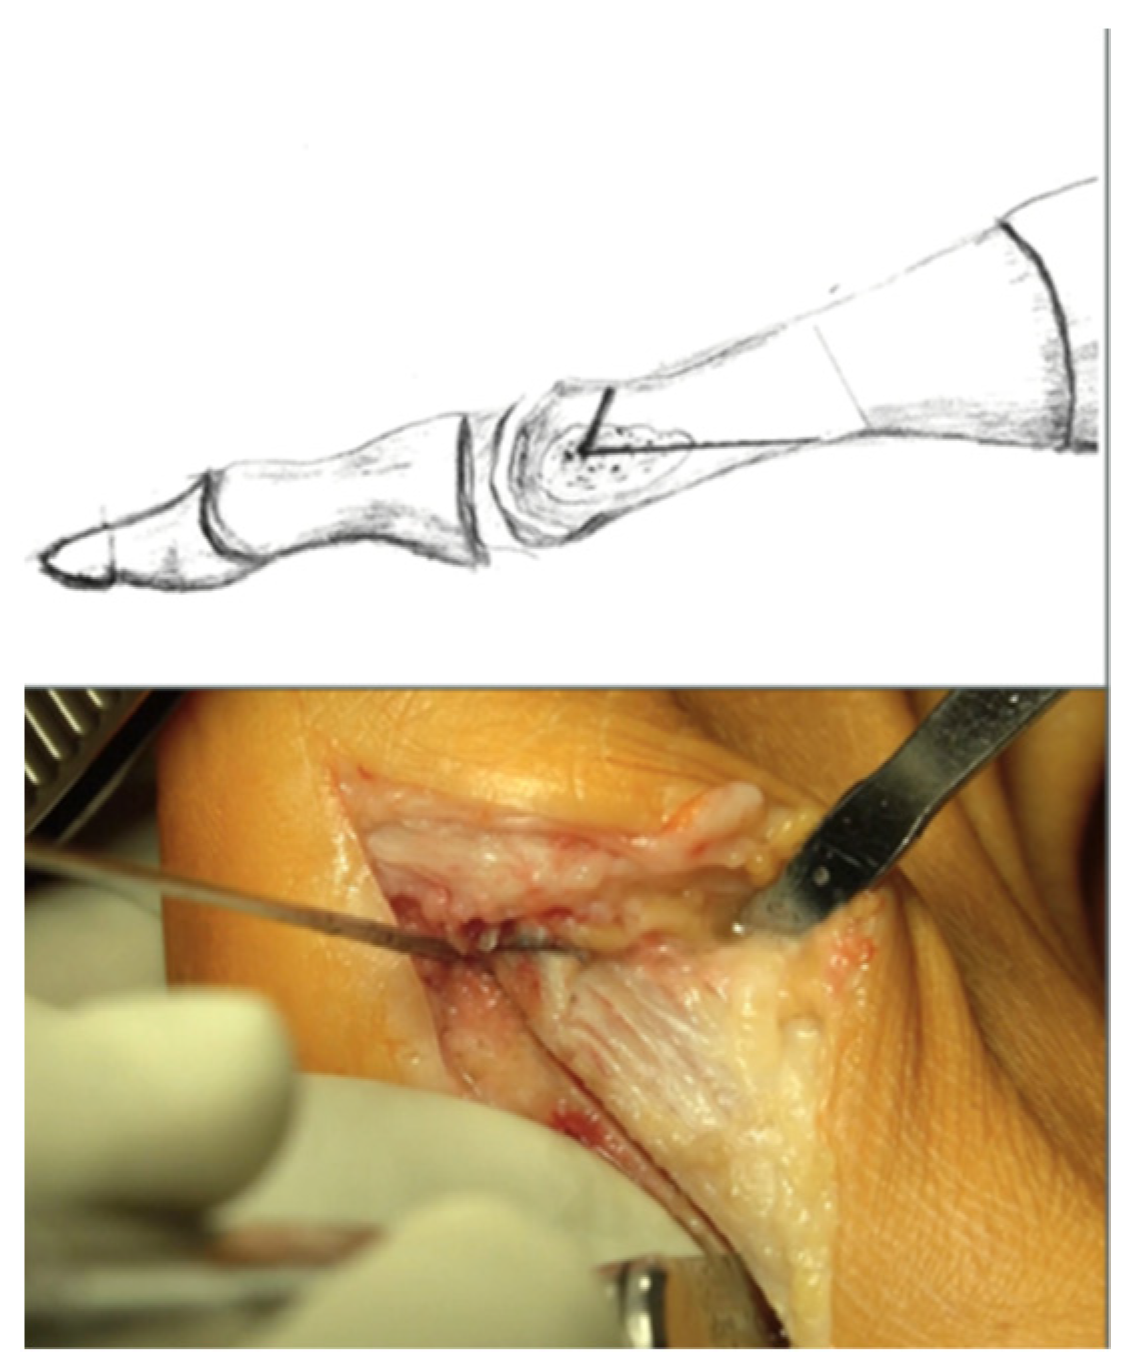

2.2. Surgical Technique and Follow-Up Treatment